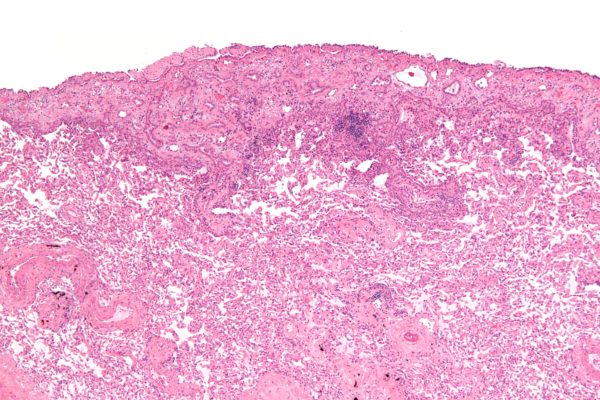

No matter how they were obtained, all biopsy and fluid samples are sent to the pathology lab. There, a doctor will look at them under a microscope and test them to find out if they contain cancer cells (and if so, what type of cancer it is).

It is often hard to diagnose mesothelioma by looking at cells from fluid around the lungs, abdomen, or heart. It can even be hard to diagnose mesothelioma with tissue from small needle biopsies. Under the microscope, mesothelioma can often look like other types of cancer. For example, pleural mesothelioma may resemble some types of lung cancer, and peritoneal mesothelioma in women may look like some cancers of the ovaries.

For this reason, special lab tests are often done to help tell mesothelioma from some other cancers.

Immunohistochemistry: This test looks for different proteins on the surface of the cells or inside them. It can be used to tell if the cancer is a mesothelioma or a lung cancer, which can sometimes appear to start in the inner lining of the chest.

If mesothelioma is diagnosed, the doctor will also determine what type of mesothelioma it is, based on the patterns of cells seen in the microscope. Most mesotheliomas are classified as either epithelioid, sarcomatoid, or mixed/biphasic.